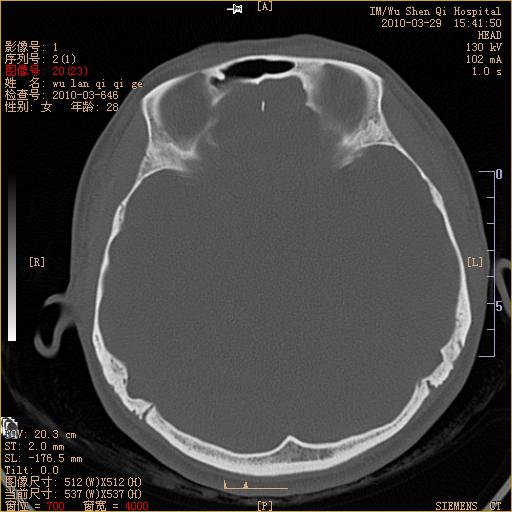

标题: CT25398:女,左耳流脓两年余,带有异物 [打印本页]

标题: CT25398:女,左耳流脓两年余,带有异物

左侧中耳乳突炎,不排除胆脂瘤形成。

左侧中耳乳突炎,胆脂瘤形成。

左侧中耳乳突炎,不排除胆脂瘤形成

1)左侧慢性中耳乳突炎并肉芽肿(或胆脂瘤)形成。2)考虑左侧颞骨慢性炎症伴骨质增生硬化,不排除骨纤。